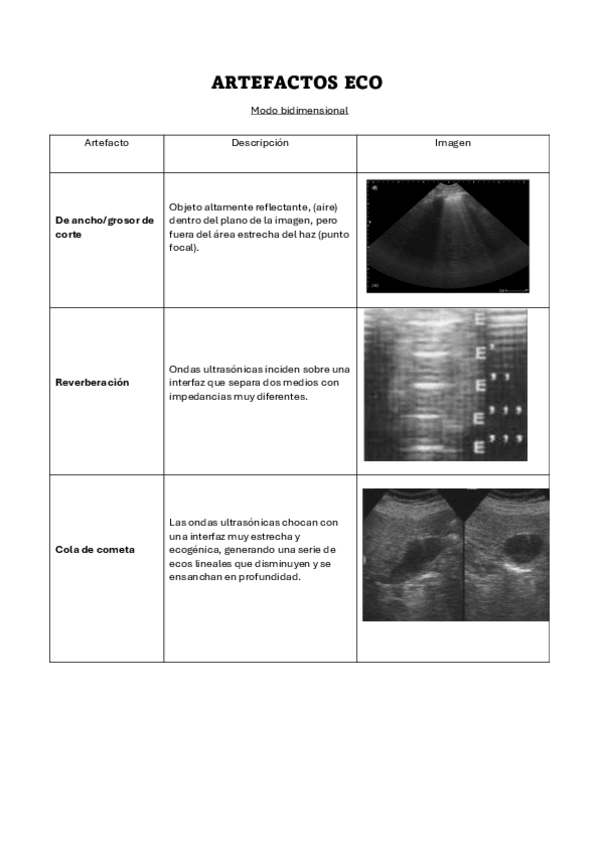

He publicado nuevos apuntes de Técnicas de Tomografía Computarizada y Ecografía: Artefactos-ECO.pdf

He publicado nuevos apuntes de Técnicas de Tomografía Computarizada y Ecografía: Artefactos-ECO-modo-bidimensional.pdf

3 páginas